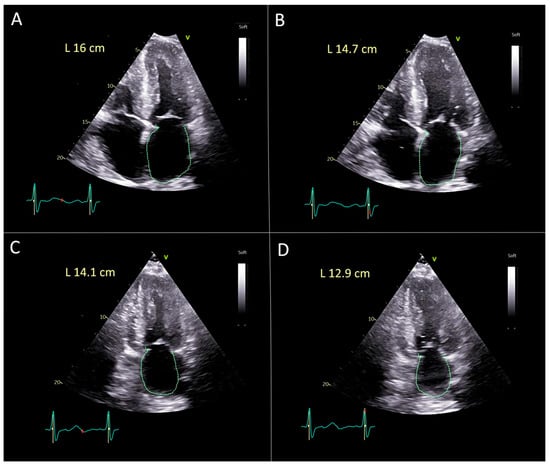

Validation of Manual Method for the Left Atrial Strain Calculation